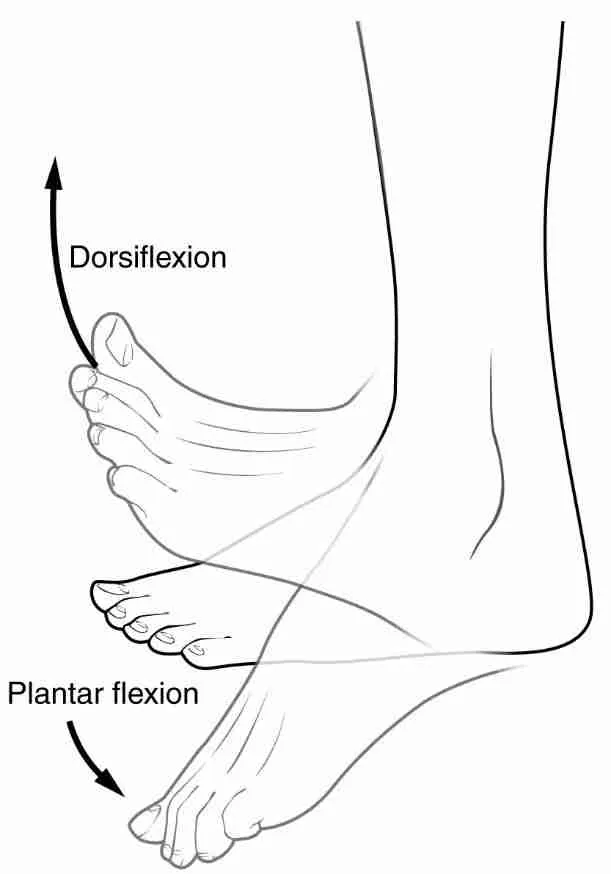

what are the motions of the talocrural joint?

plantar flexion

dorsiflexion

in what plane does dorsiflexion and plantar flexion occur?

sagittal plane